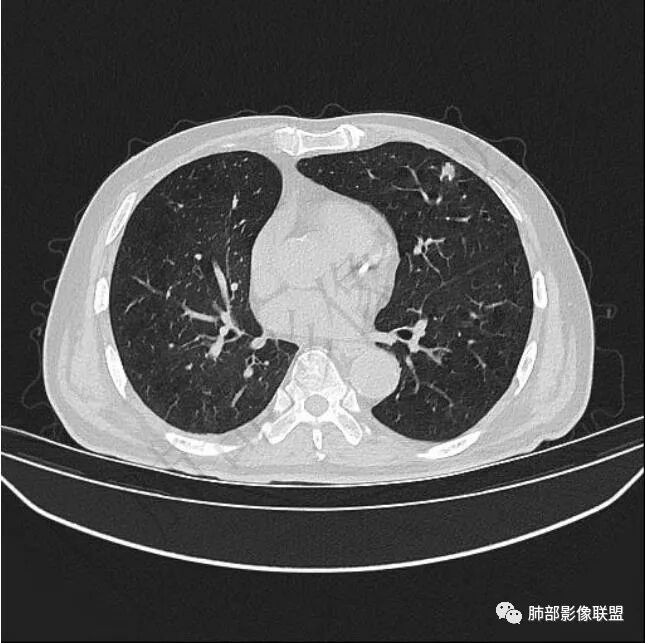

二..发现左肺上叶舌段实性密度小结节影,不规则略呈半环形,边界清楚,未见分叶、毛刺及磨玻璃晕。未见卫星病灶。